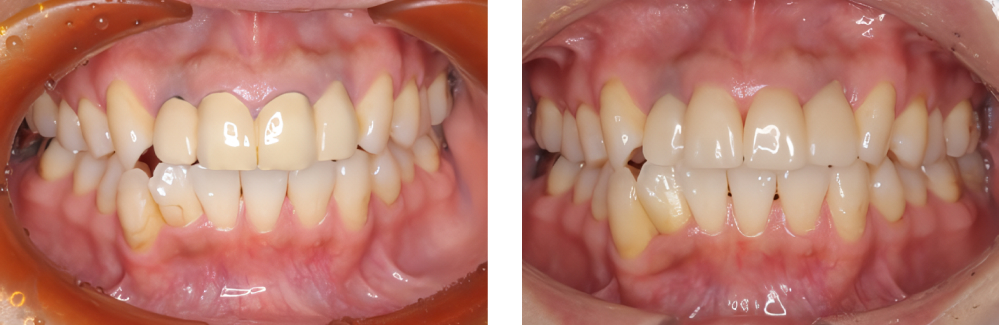

審美歯科

術前

術後

| 治療内容 | MTM後抜歯を行い上下顎前歯部に対してジルコニアセラミックにて治療を行った |

|---|---|

| 治療期間・回数 | 約1年6カ月・23回 |

| 費用 ※自由診療となります |

プロビジョナルレストレーション:2,200円×5 ファイバーコア:16,500円×2 ジルコニアセラミック:132,000円×10 |

| リスク・副作用 |

|